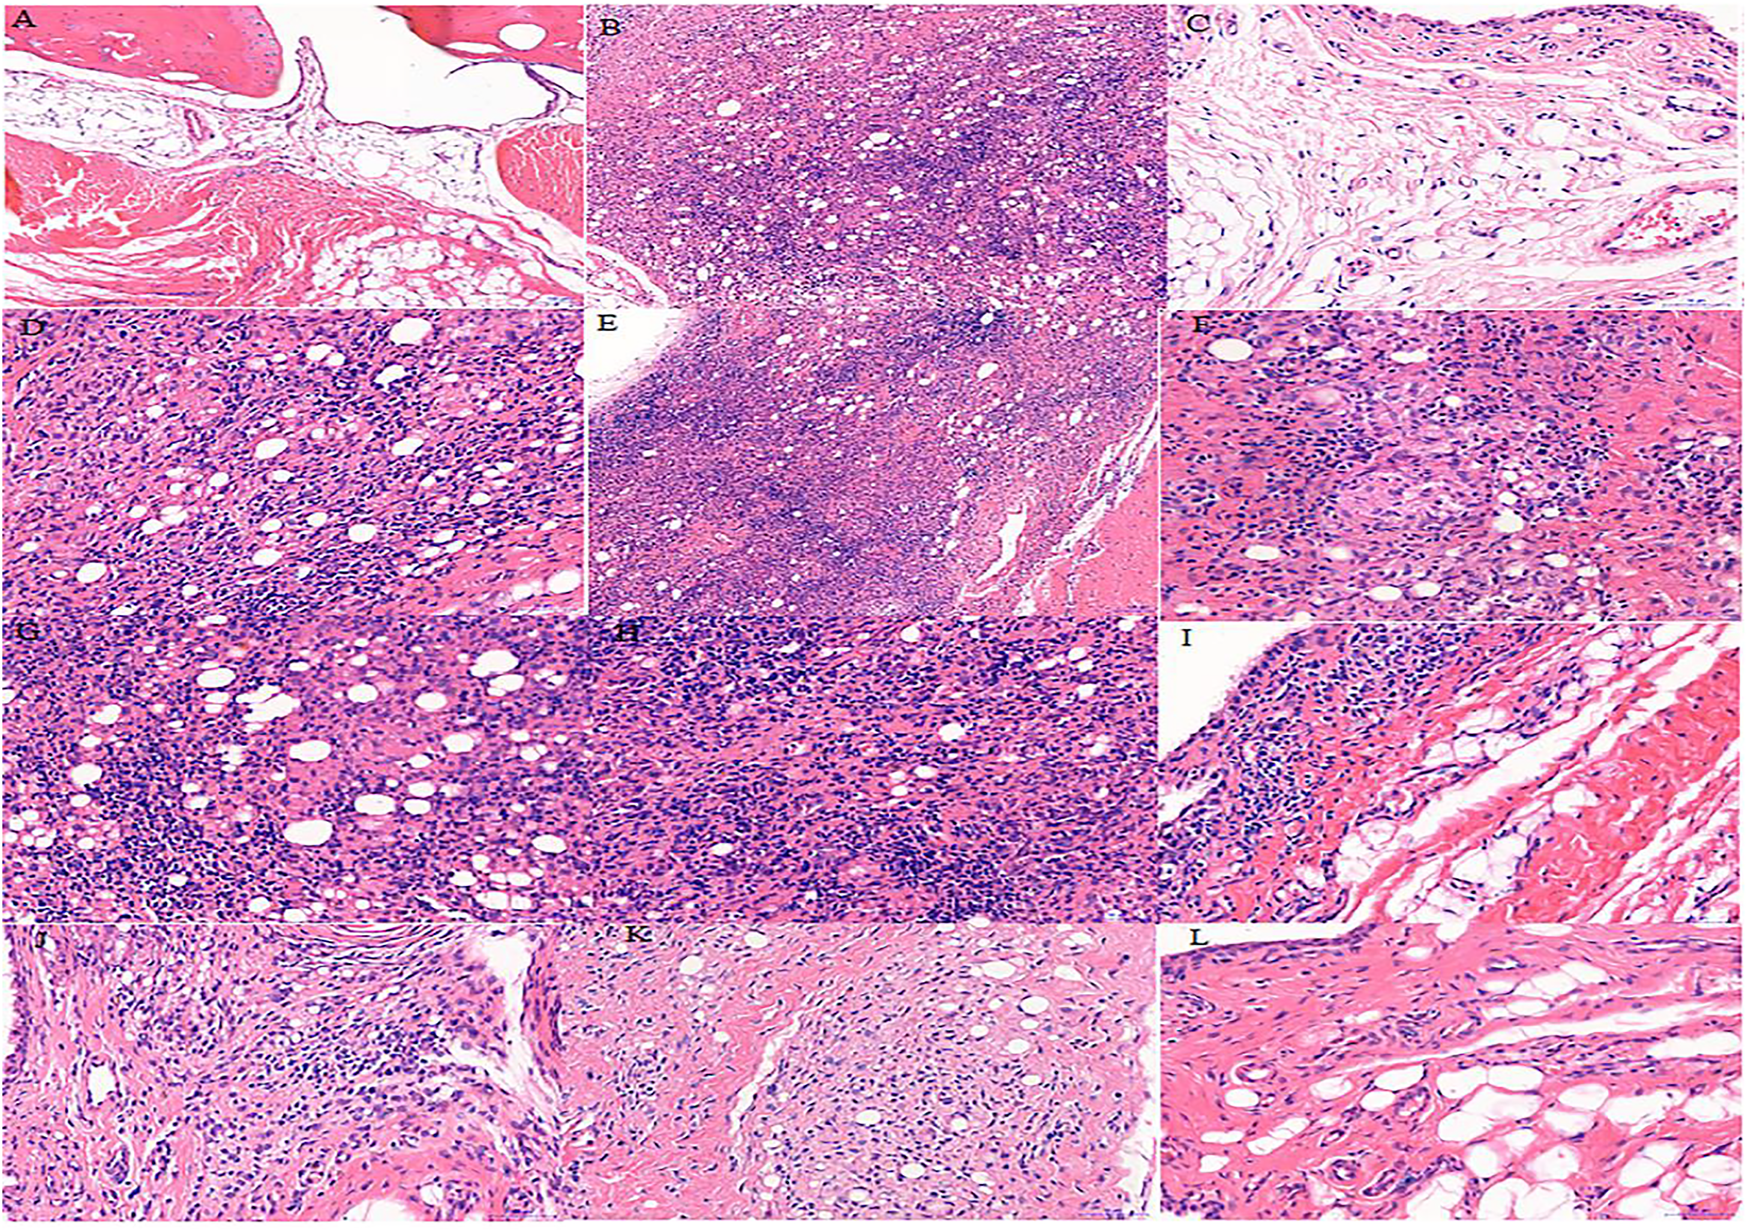

Effects of S. parviflora Wall. Leaf Extracts on Histopathological Changes in Rat Synovial Tissue

The cells in the synovial tissue of the normal group were arranged orderly, without inflammatory cell infiltration and vascular proliferation, and the articular cartilage was smooth without damage (Figure 3A). The synovial tissue of the RA model group rats showed obvious synovial hyperplasia, disordered arrangement, and local joint fibrosis. The inflammatory cell infiltration appeared in the synovial stroma and small blood vessels increased in the lower synovial layer, resulting in the formation of a large number of pannus (Figure 3B). Compared with the model group, the n-butanol fractions (0.64 g/kg, 0.32 g/kg, and 0.16 g/kg) and ethyl acetate fraction (0.64 g/kg) of the 70% alcohol-soluble fraction of S. parviflora Wall. leaves reduced the pannus in the synovium and local inflammatory cells after treatment for 3 weeks (Figures 3I–L).

FIGURE 3

Histological examination of rat synovial tissue in different groups. A, B, and C represent normal group, model group, and positive group (dexamethasone), respectively. D, E, and F represent low-dose, middle-dose, and high-dose of fraction of petroleum ether extract, respectively, G, H, and I represent the low-dose, middle-dose, and high-dose of fraction of ethyl acetate extract, respectively, and J, K, and L represent the low-dose, middle-dose, and high-dose of fraction of n-butanol extract of 70% alcohol-soluble fraction of S. parviflora Wall. leaves, respectively.